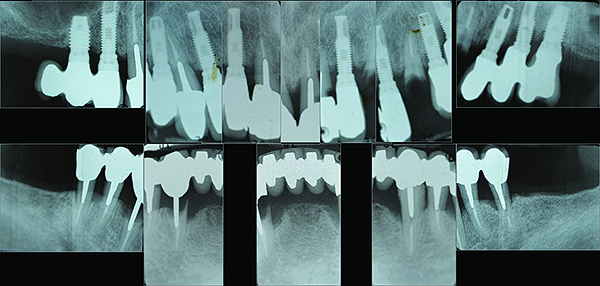

After initial consultation, the preoperative full-mouth radiographs were obtained from the referring periodontist (Figure 1). To address the immediate concern of the patient, replacement of the original crown on tooth No. 11 was provisionally secured to the supporting root. Diagnostic study casts were made of the existing clinical conditions (Figure 2). A complete dental and medical assessment and identification and explanation of treatment objectives was performed. The patient was referred back to the periodontist for confirmation of the implant and periodontal treatment proposals. This included a cone-beam computed tomography (CBCT) scan of the mandible (Figure 3) to aid in optimal implant placement.8 This was then coordinated with the development of the prosthetic sequencing and design. After presentation of the completed treatment plan to the patient, informed consent was obtained.

The maxillary prototype was adjusted, polished, and left to function with the mandibular provisional. The definitive maxillary zirconia restoration was then completed from the information provided by the prototype, and the cutbacks for the facial porcelain (Nos. 6 through 11) were done after milling but before sintering. Subsequently, the mandibular prototype was adjusted to the sintered and colored maxillary zirconia framework before the application of porcelain to Nos. 6 through 11 and final glazing (Figure 11). Following this step, the mandibular definitive monolithic zirconia restoration was milled, colored, and sintered. The facial porcelain (Nos. 6 through 11) was applied, and then both maxillary and mandibular restorations were stained and glazed (Figure 12). Both bridges were inserted at the same time (Figure 13 through Figure 15). Minor occlusal adjustments and oral hygiene access was verified and the zirconia surfaces polished. The bridge screws were torqued to 20 Ncm according to the manufacturer’s recommendation, and No. 24 was luted with a provisional cement. Postoperative radiographs were taken (Figure 16).

Fig 1. Pre-treatment full-mouth radiographs.

Figure 1

Fig 16. Post-treatment full-mouth radiographs.

Figure 16